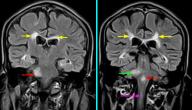

يُعد التصوير بالرنين المغناطيسي للدماغ (MRI) أحد الطُرق الرئيسية لتشخيص ضمور المخيخ، تليه الاختبارات خزعة العضل، ودراسة الجهاز العصبي المحيطي للطفل المُصاب،[٤] كما قد يوصي الطبيب بفحوصات أخرى تتضمن ما يأتي: